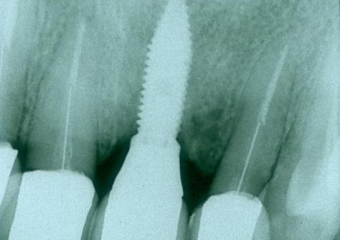

Raio X do implante e prótese fixa em porcelana